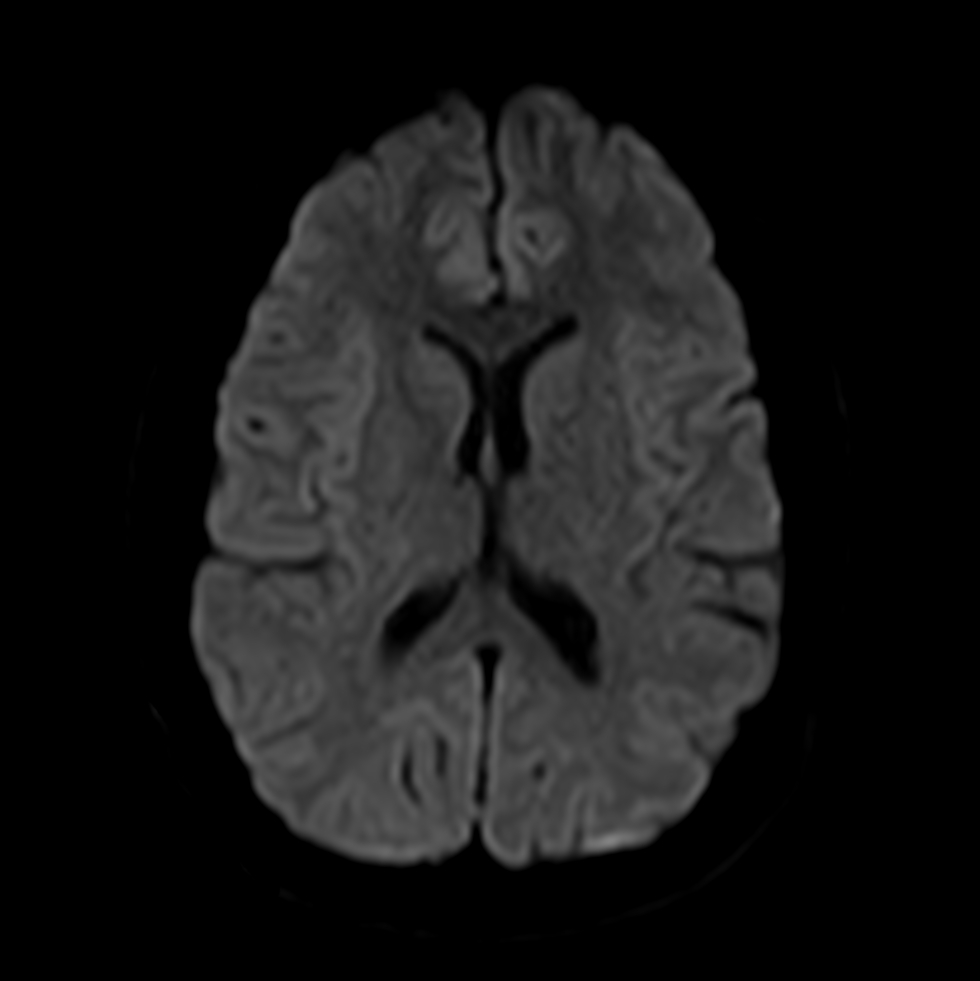

Axial DWI (b1000)